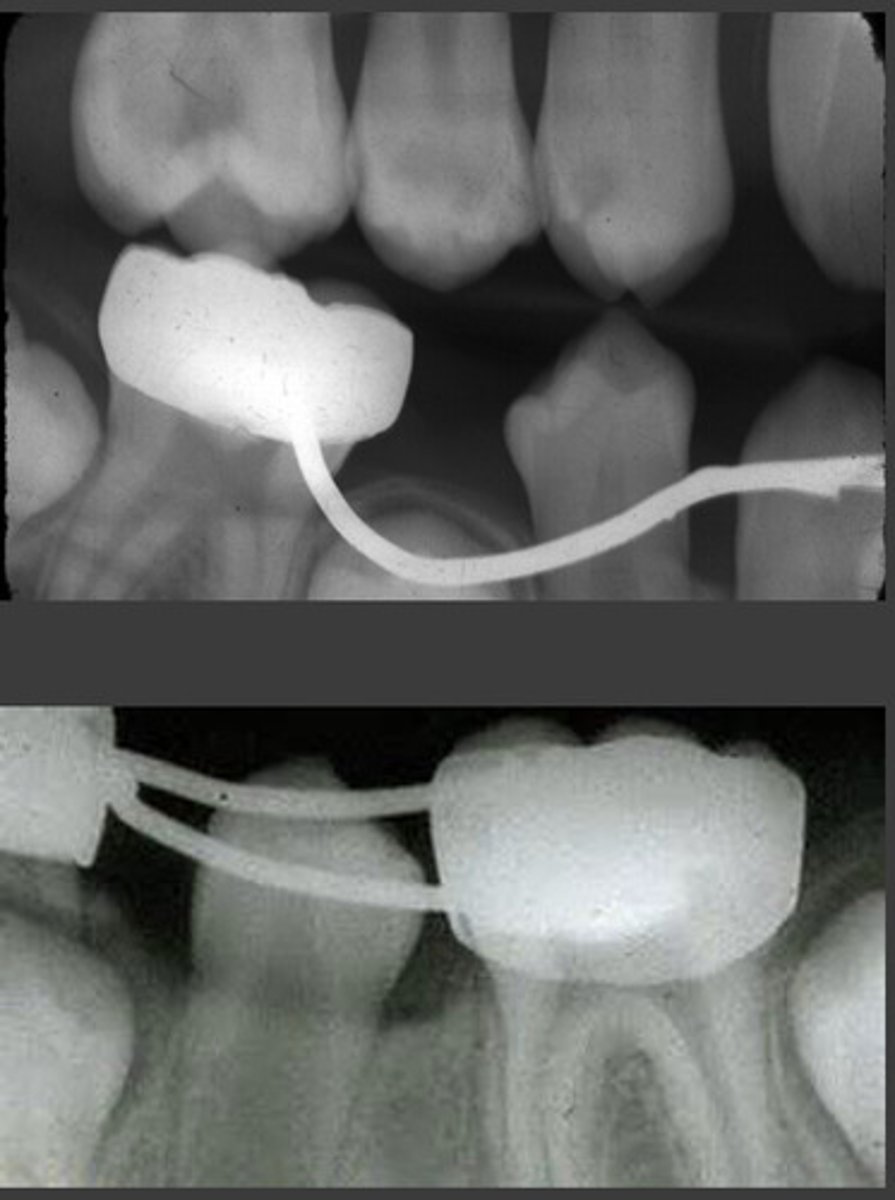

space maintainer